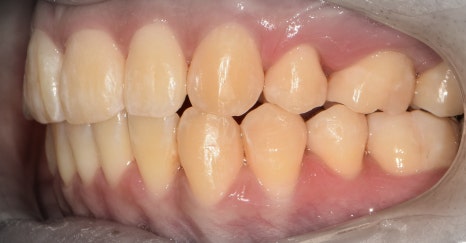

측면에서는 크게 2가지를 느낄 수 있습니다.

- 전치부 치아들의 치축, 전방 뻐드러짐

- 1치대 1치의 관계

*정상이라면, 1치대 2치의 관계를 가져야 됩니다.

또한, 측절치 및 송곳니의 총생들도 같이

관찰을 할 수 있습니다.

앞서, 1치대 1치 관계에 있던 교합관계들이

1치대 2치의 관계로 바뀐것을 볼 수 있으면서

길쭉하게 느껴졌던, U shape 형태의 악궁이

딱 보기 좋은, U shape 로 바뀌었죠.

이 분은, 코는 높고 예쁘셨기 때문에

조금 더 세련 된 얼굴형을 갖게 되셨습니다.